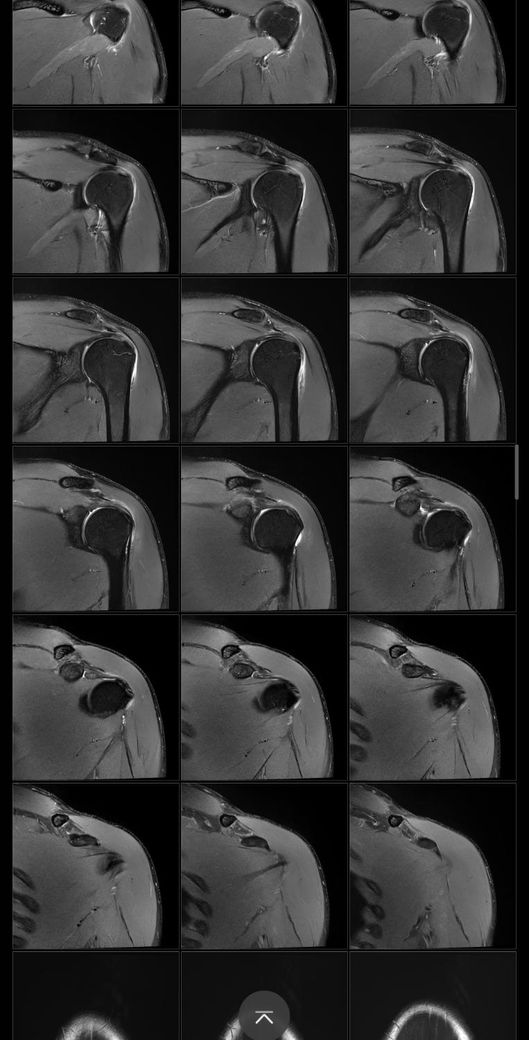

어깨 mri 전문의 소견 부탁드립니다

얼마전에 축구하다가 넘어지고 그날 저녁부터 팔이 안올라가서 건협가서 mri 찍었습니다.

회전근개 파열이 있는지, 없다면 지금 상태가 어떤상태인지와 웨이트 운동 가능할정도의 회복기간이 궁금합니다

• 8번 째 사진

Mri에서 별다른 이상소견이 없는 경우 일시적으로 발생하는 움직임이나 기능의 제한일 수 있습니다.

약 2주 이내의 회복기간이 소요될 수 있으며, 현재 mri 사진에서 보이는 염증 소견은 타박상으로 인해서 발생하는 것일 수 있습니다.

별다른 파열의 징후는 보이지 않습니다.

질문하신 내용 잘 읽어보았습니다. MRI결과에서 회전근개 파열 여부가 핵심입니다 부분 파열과 염좌라면 보존적 치료후 6~8주 내 웨이트 복귀 가능하지만 완전파열이면 수술 후 최소 3~6개월 재활이 필요합니다. mri 판독 결과지를 확인해야 정확한 상태와 회복 기간을 판단할 수 있습니다!